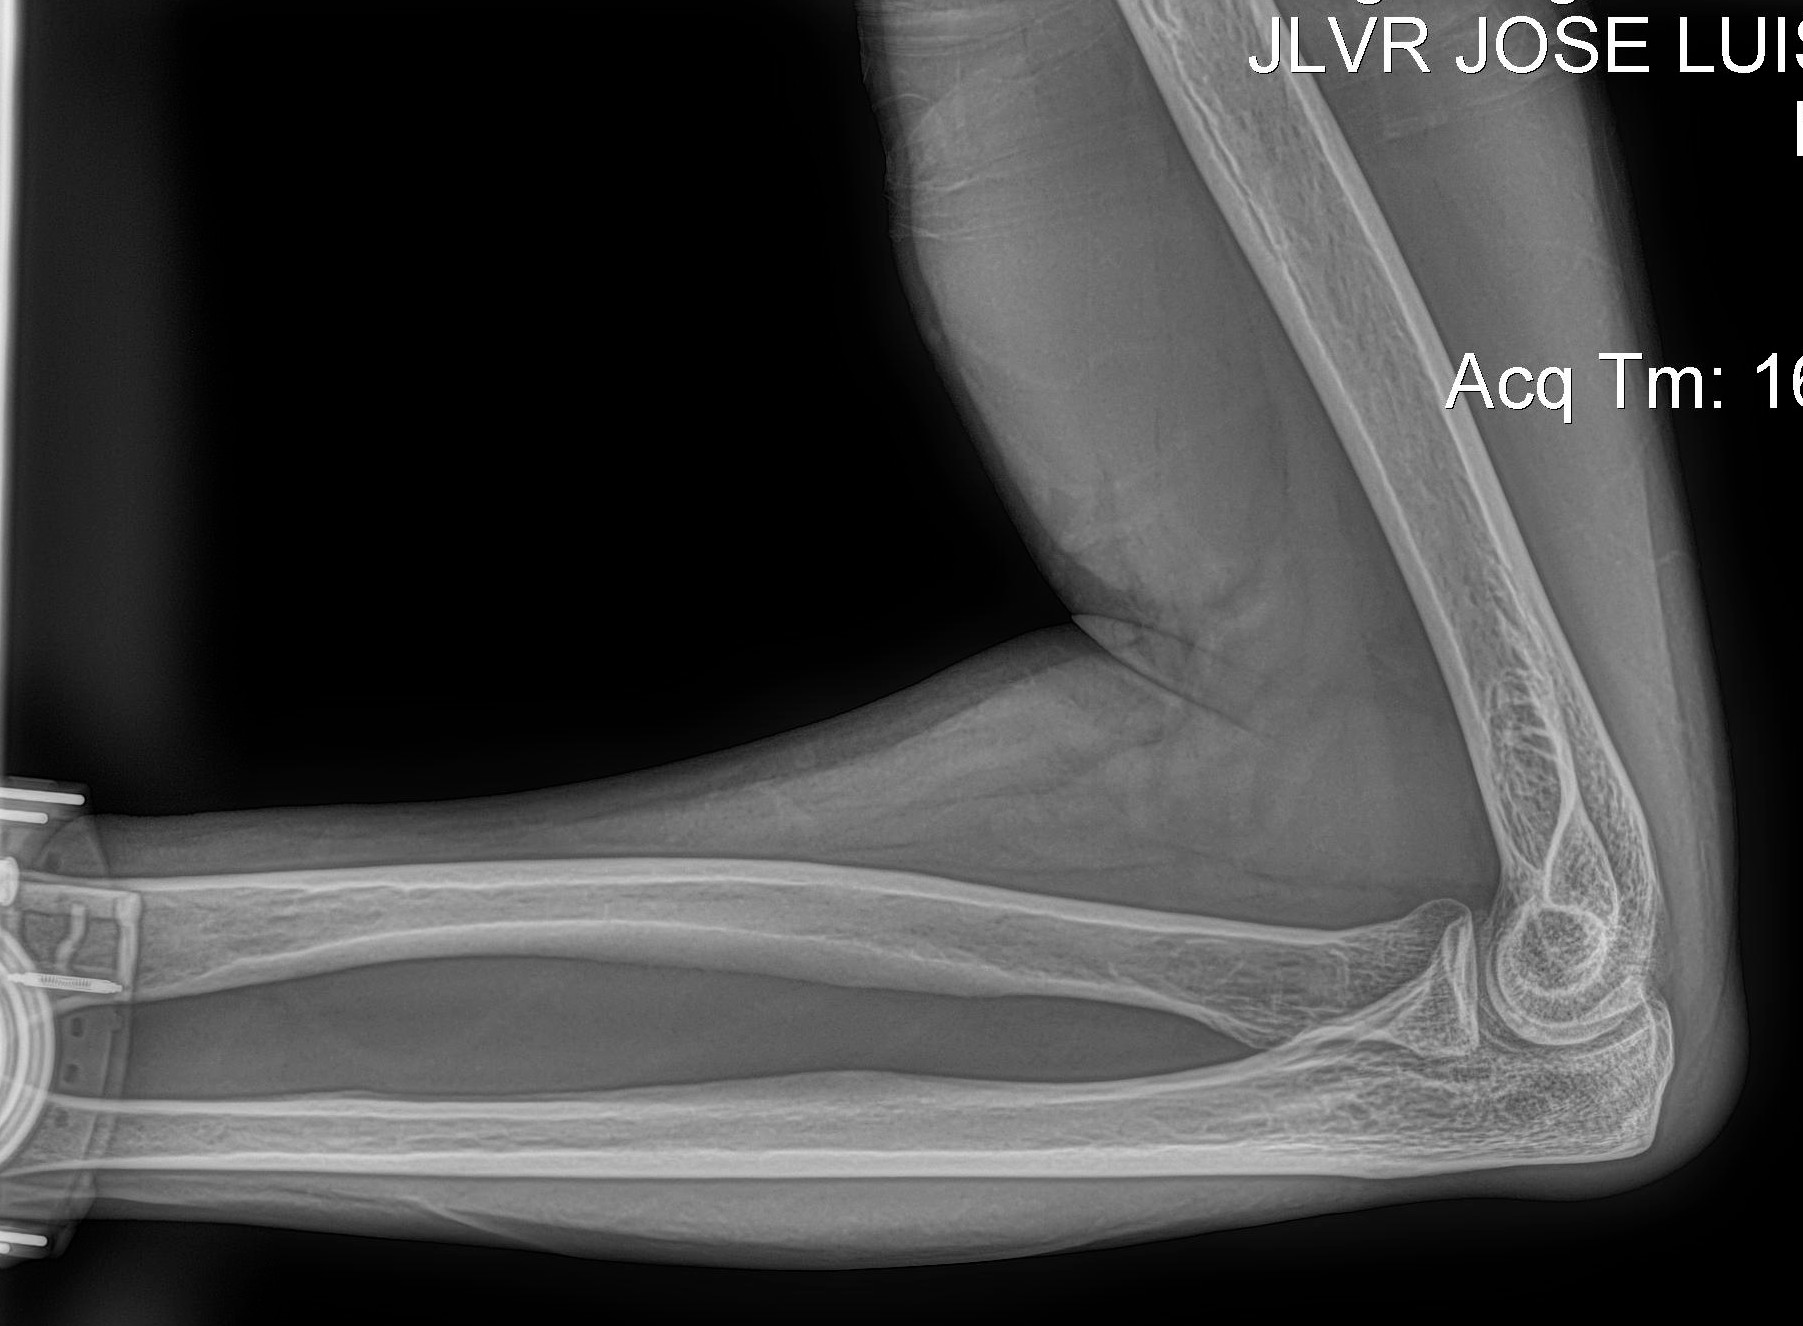

Radiología Digital como Herramienta Complementaria en el Dictamen de Bienes Muebles

Cambios Térmicos en las Extremidades de Caballos,

Asociados a Golpes y su Evaluación por Termografía.

Los caballos de salto, en competencia, pueden derribar obstáculos y lastimarse. Si se golpean, no siempre claudican. Considerando al calor como un signo de inflamación, se evaluaron los cambios térmicos de 6 áreas de las extremidades torácicas y pelvianas de 23 caballos de salto en nivel de competencia de 1.05 a 1.60 m de altura, por medio de termografía durante 4 días de competencia (N=2208 áreas).